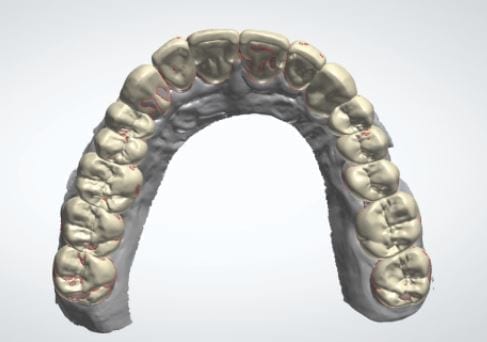

Over the course of a few appointments, the vertical dimension was reduced and the temporaries were adjusted to the patient’s desires. The new upper and lower arch were captured with the Medit i500 and the jaws were related to each other.

This was then imported into exocad where the prepped arches from a few weeks prior were force matched to the new bite

The case was designed by CADENT BESSA, and the models were printed by Burbank Dental Lab with Carbon Printers. There restorations were milled and cut back and layered by Burbank Dental Lab